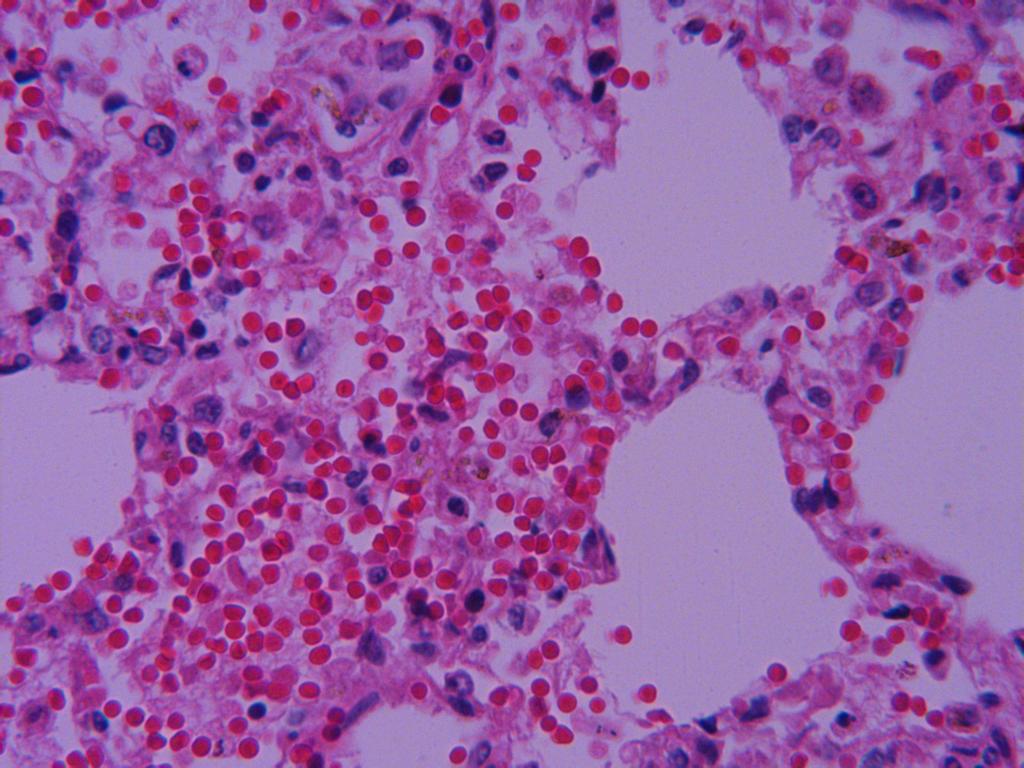

纤维素性肺炎

肺泡腔有大量淡红染的浆液和纤维素,并可见数量不等的红细胞和肺泡壁上皮细胞。

肺泡腔有大量红染的浆液,肺泡壁毛细血管扩张充血。

肺泡腔有浆液和纤维素,肺泡壁毛细血管扩张充血。

肺泡壁毛细血管扩张充血